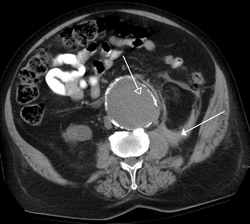

When evaluating hepatic masses, it can be advantageous to have both late arterial and portal venous phase images (biphasic imaging, figure 4) since some tumors enhance briskly during the arterial phase (hepatocellular carcinoma, hepatic adenoma, follicular nodular hyperplasia (FNH), and hypervascular metastasis), but may be occult or difficult to characterize on portal venous phase imaging alone (figure 6). However, it should be stressed that the addition of late arterial phase images is only indicated if one of these tumors is suspected, or if there is a need for further characterization of a hepatic mass, since the large majority of patients will not benefit from the addition of this phase. In addition, if there is a need to definitively characterize a hepatic mass, MRI is generally more sensitive and specific, with no associated radiation dose.[citation needed]

The late arterial phase is timed to correspond to the peak concentration of contrast material in highly vascular tumors and is performed approximately 20–35 seconds after the injection of intravenous contrast. Early arterial phase imaging is predominantly utilized for angiography and will be discussed separately. Late arterial phase imaging is almost always performed in conjunction with other phases (e.g. portal venous phase) to allow more complete characterization of any identified abnormalities (figure 4). The primary indication for a late arterial phase is for the evaluation of hypervascular tumors of the liver such as hepatocellular carcinoma or hypervascular metastases (figure 4). Typical hypervascular tumors for which this would be used include: hepatocellular carcinoma; renal cell carcinoma; melanoma; carcinoid/neuroendocrine tumors; some sarcomas; choriocarcinoma; and thyroid carcinoma. Although a “hypervascular”, biphasic evaluation would generally be used for these patients, note that a single phase is often adequate for follow up imaging.[citation needed]